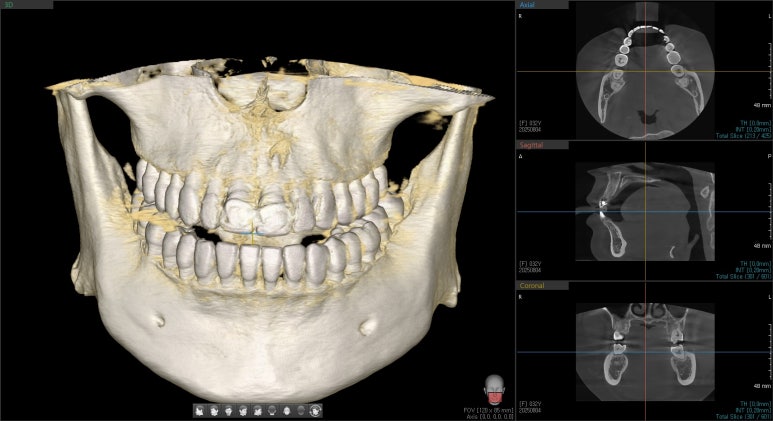

엑스레이 검사 결과, 뿌리 끝에는 염증도 생겨 있었습니다.

단순히 겉모습의 문제만이 아니라, 치아 뿌리 쪽도 치료가 필요했던 상황이었습니다.

치료는 재신경치료와 BOPT컨셉을 이용한 크라운 재치료로 계획했습니다.